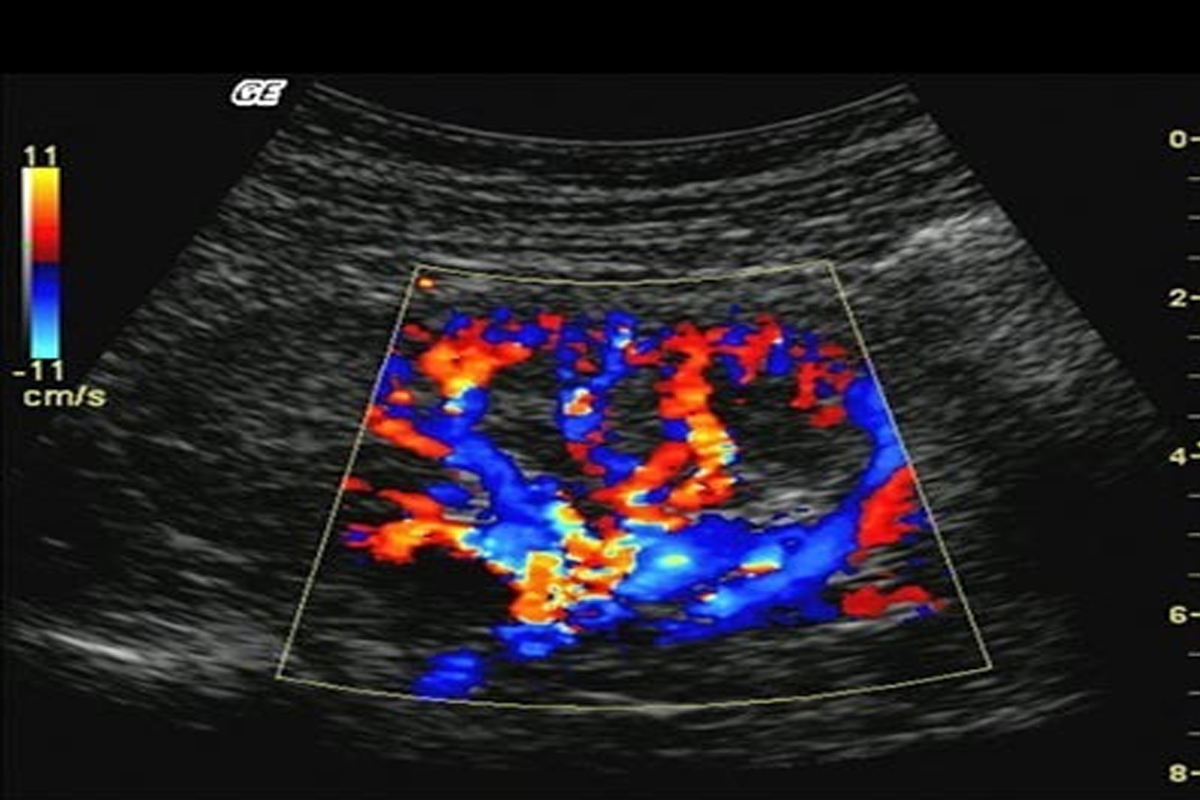

Colour Doppler

This type of Doppler uses a computer to change sound waves into different colors. These colors show the speed and direction of blood flow in real time. Power Doppler, a newer type of color Doppler. It can provide more detail of blood flow than standard color Doppler.